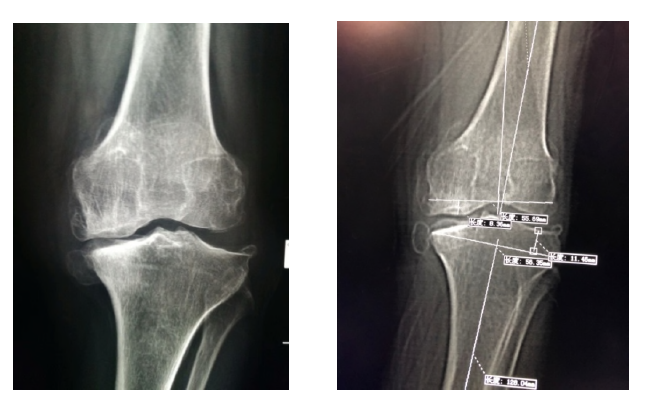

術前手術規劃